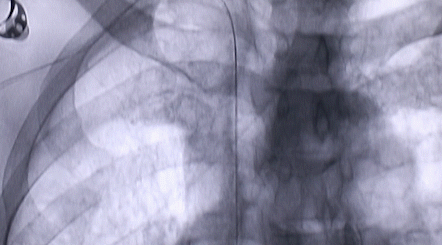

按照術(shù)前制定的方案,郭穎強(qiáng)主任和楊金保博士首先嘗試開通閉塞的右腎動(dòng)脈,但由于血栓機(jī)化、鈣化嚴(yán)重,右腎動(dòng)脈難以開通。遂謹(jǐn)慎擴(kuò)張狹窄的左腎動(dòng)脈,并成功植入一枚支架。之后經(jīng)過(guò)反復(fù)旋磨、抽吸,順利開通髂動(dòng)脈,但腹主動(dòng)脈閉塞段仍難以擴(kuò)通。此時(shí),患者居高不下的血壓很快恢復(fù)到正常水平。